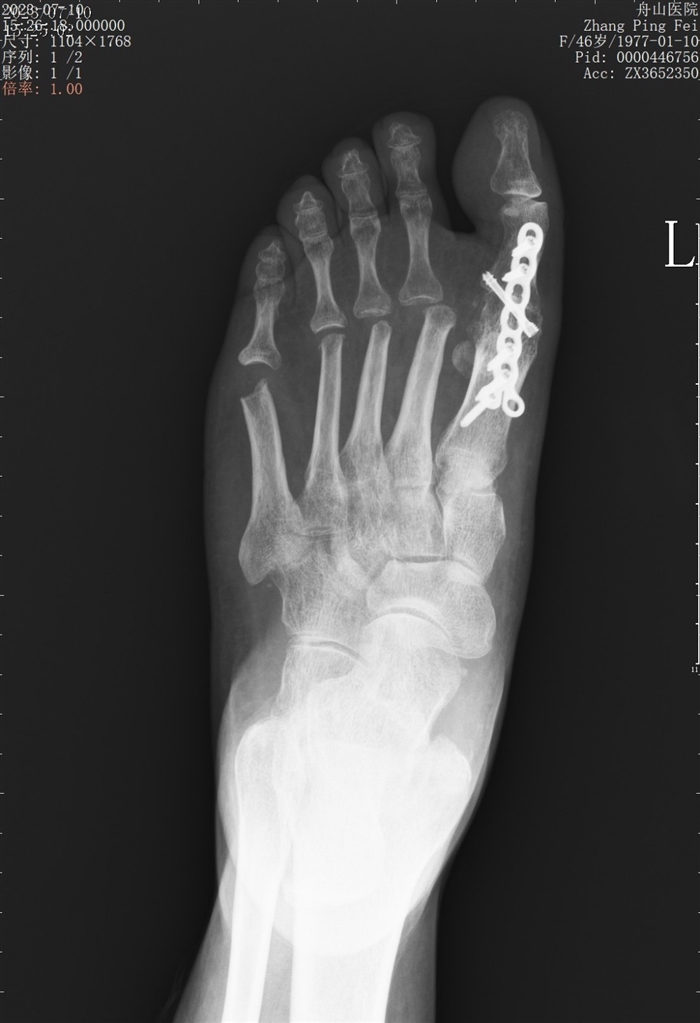

拇外翻手术前后

去年,舟山医院收治了一例严重拇外翻的女性患者。患者多年来一直有穿鞋尴尬,因为她两只脚的大脚趾都朝小脚趾倾斜,夏季就只能穿宽大的运动鞋或布鞋来遮挡。随着年龄增长,她走路时足部俞愈发疼痛,已严重影响正常生活,不得已到舟山医院就诊。

“这个患者的拇外翻已经发展得很严重了,除了拇趾,其他几个脚趾也出现了变形,第4趾还骑跨于第5趾,后来的手术就相对大一些。如果是轻度的拇外翻,是可以采用保守治疗的。”

对于一些市民有手术疼痛、术后恢复相关的担忧,朱晓波表示,拇外翻手术的创口不大,切口一般在3厘米左右。疼痛也比一般骨折手术轻很多。“术后一般3~7天就可以穿前足减压鞋下地行走,平时坐办公室上班的患者一般在术后5~7天就能返工。”对于从事需要长时间站立、行走工作或需穿高跟鞋的患者,朱晓波则建议,等到截骨完全愈合后再上班,愈合时间一般为6~8周。做过拇外翻手术的患者换药时要尽量选择足踝外科医生而非普通外科,因为对应科室在包扎手法上有所讲究。“另外,我们也建议有拇外翻遗传史的人群,定期到医院做检查,观察一下有没有发展迹象。”